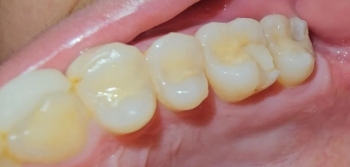

The Foundation: Surgeons remove one of the patient's teeth—often a canine—along with a portion of the surrounding jawbone and ligament. This tooth-bone unit is then meticulously sculpted and a tiny, custom optical lens is inserted into its center.

Structural Integrity: Teeth are the hardest substances in the human body. They are designed to withstand a lifetime of incredible force, making them a surprisingly durable anchor.